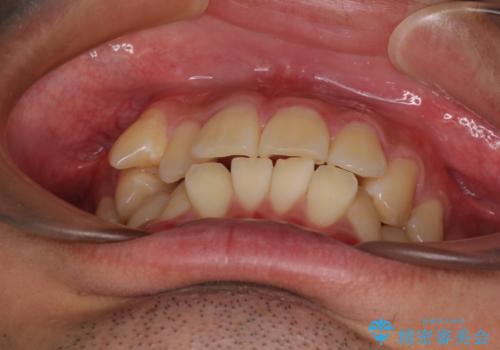

- 前歯のデコボコと右上の八重歯を気にして来院された患者様です。

口元が突出する仕上がりとならないように、舌突出癖改善のトレーニングをしっかりと行っていただきながら、矯正治療を進めていくこととしました。